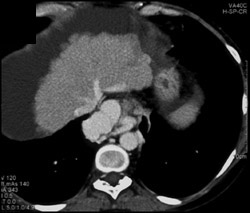

Esophageal Varices